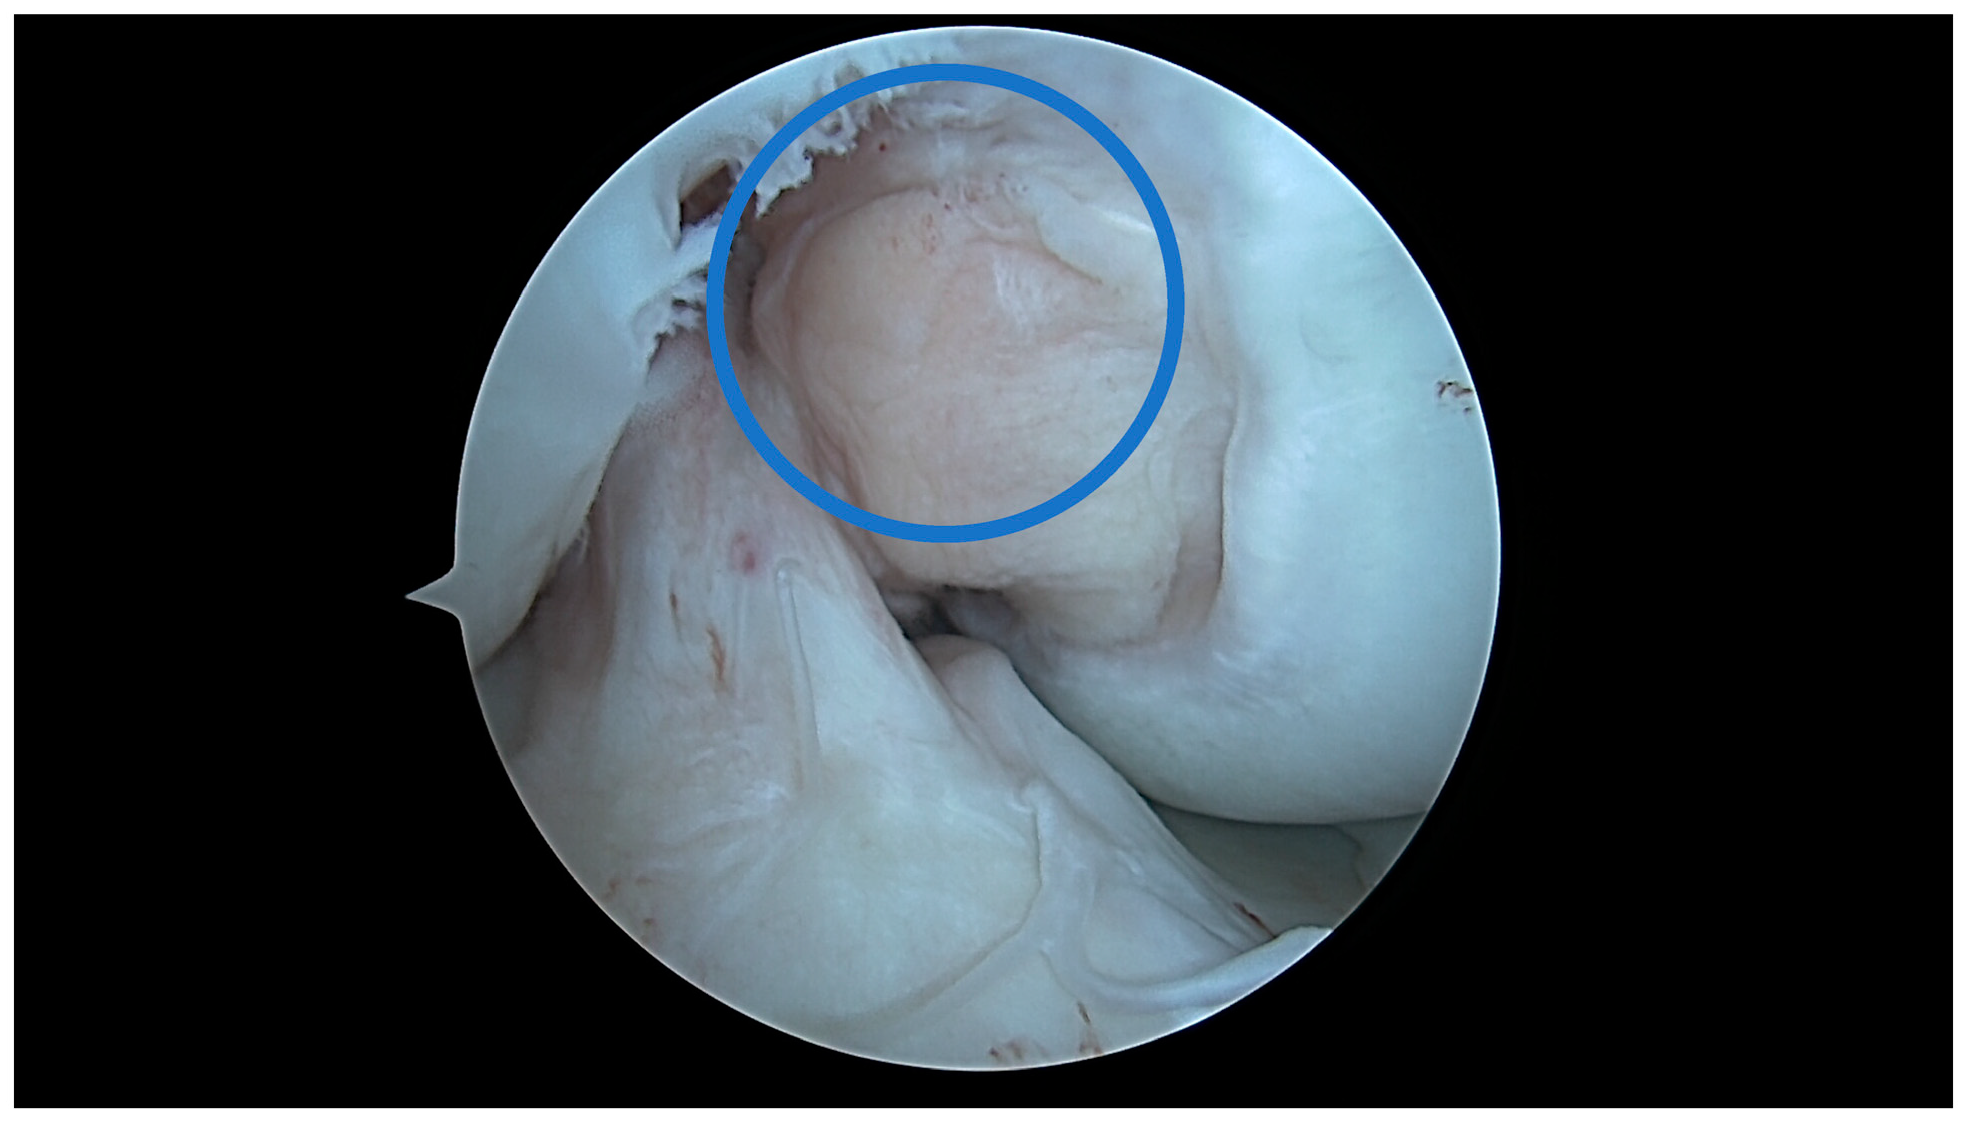

4.1. U-Shaped Notch

4.2. A/W Shaped Notch